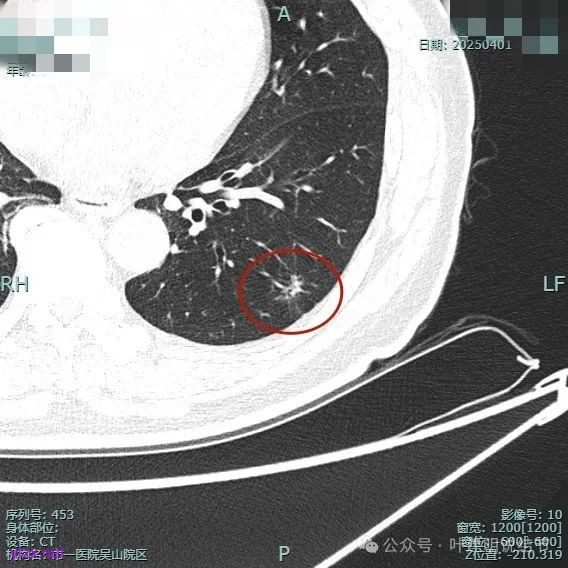

病灶毛刺空泡(或细支气管扩张)都有,表面不平,灶内杂乱。

但纵向看是偏条状些的,密度较高,边上有少许磨玻璃成分,磨玻璃部分略显模糊。

中间实性部分密度过高,边上的的毛刺显得过长,且不太锐利。

实性成分密度较高,边上有淡磨玻璃成分,毛刺明显。

密度高,边上磨玻璃成分淡,表面不平,毛刺不太锐利,整体感觉缺乏收缩力。

相应支气管有扩张,边上的磨玻璃成分偏糊,界限欠清。

进入的血管没有异常增粗,棘突不太锐利,磨玻璃成分偏糊。

上图倒是血管显得有点异常增粗的,总体膨胀性不强,收缩力不够。

我的意见是纵向看线状,考虑慢性炎伴纤维增生可能性大些,建议4-6个月复查。